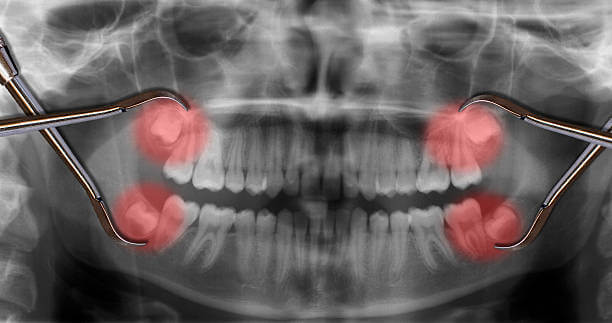

인류의 턱이 작아지면서 입안 깊숙이 사랑니가 자랄 공간이 부족해졌고 이 때문에 사랑니는 눕거나 발치하는 등 썩거나 염증이 생기기 쉬운 모양으로 나오는 경우가 많습니다.

인간은 사랑니를 제외하고 상하 14개의 영구치를 가지고 있습니다. 중앙에 한 쌍의 앞니, 한 쌍의 옆 앞니, 한 쌍의 송곳니, 두 쌍의 작은 어금니, 두 쌍의 어금니가 있습니다. 이 두 어금니보다 작고 큰 어금니 바깥쪽으로 자라는 치아를 '사랑니'라고 합니다. 사랑니의 학명은 '제3대구치'로 세 번째로 큰 어금니를 의미합니다.

사랑니가 다 있게 되면 위턱과 아래턱 양쪽에 하나씩 총 4개가 됩니다. 약 7%의 사람들은 사랑니가 전혀 없으나 만약 가지고 있다면 치아의 수는 사람마다 1~4개로 다양합니다.

때때로 사랑니가 뼈에 묻혀서 그 주위에 낭종과 같은 것을 일으켜 뼈를 손상시키기 때문에 사랑니를 발치하는 경우가 많습니다. 그러나 사랑니는 뼈가 잘 발달되어 있고 잇몸으로 덮여 있지 않다면 발치 할 필요가 없다고 합니다.